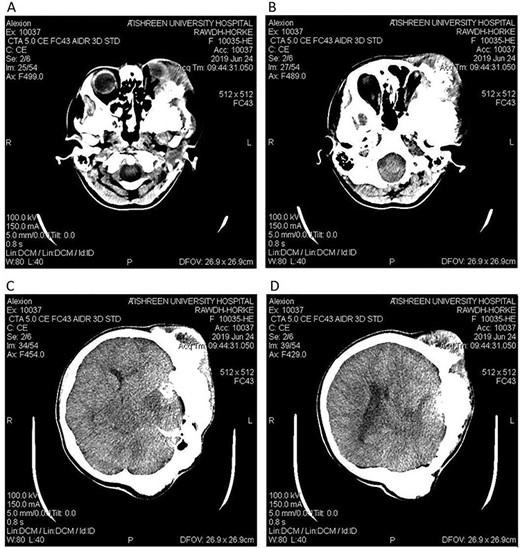

CT head tissue window. A, B. Invasion and destruction of the surrounding tissue. C. Minor shift of the elements of the midline to the right side due to the edema. D. The edema applies pressure to the left lateral ventricle.

A 17-year-old female presented with a history of osteosarcoma that was confirmed after undergoing a surgery to remove an enlarging bone tumor in the left temporal region 2 years ago. She later got pregnant and delivered her child but never got back for a checkup until she was admitted to our hospital with a severe and unresponsive to medication headache that progressed over the course of 6 months and blurred vision that progressed to complete left-sided vision loss. Physical examination revealed a tough and mobile yet fixed at the base 7-cm mass towards the left of the frontal bone. Many more masses were revealed in the left side of the skull including the anterior cranial fossa, orbit, base of the skull and the left part of the occipital region where the previous procedure was performed (Fig. 1). These masses had been increasing in size probably under the influence of pregnancy hormones causing pain that radiated along the orbital and maxillary branches of the left trigeminal nerve. Physical examination and past medical history were otherwise unremarkable. Laboratory tests were all normal, and her family history was negative. Staging studies showed no evidence of distant metastatic disease in the chest, the abdomen and the pelvis. CT scan of the skull revealed a bone-forming non-lytic lesion accompanied by periosteal reaction. This lesion bulges to the outside towards the scalp spreading into both the soft tissues and the inside of the entire left side of the skull with a sunburst-pattern (Figs 2 and 3). Its rims are unsymmetrical and pointy, and it bulges into the left orbit outside the muscles causing exophthalmos with a semi-complete proptosis of the eyeball out of the orbit (Figs 2 and 3). This lesion applies pressure to the left frontal and temporal lobes causing mild edema in both these lobes without invading the brain tissue. This edema in turn applies pressure to the left lateral ventricles (minor shift of the elements of the midline to the right side can be seen on CT) (Fig. 4). Due to the tumor’s wide spread, the surgical procedure was performed in two stages (approximately 6-hour-long each). In the first stage, the bone mass was removed through a procedure of wide skull approach including the frontal, temporal and parietal bones and a removal of the invading part of the temporal muscle. Moreover, the lateral wall and roof of the left orbit were removed, the left optic nerve was dissected free and part of the meninges was removed and replaced with an autogenic patch from the fascia lata. Then, the bone loss was compensated for by using bone cement Synicem VTP (poly methyl methacrylate and Barium sulfate), and the orbit was rebuilt; the eyeball was placed back with noticeable decline of the exophthalmos. In the second stage, a complementary left parietal occipital incision of the previous approach was performed 3 weeks later; the remaining of the frontal and occipital bones was removed, and a partial mastoid surgery was done. Furthermore, the cavernous sinus were revealed and found to be not invaded. Later on, the normal skull shape was restored using the same cement. The histopathology of the lesion revealed proliferation of neoplastic chondroblasts, osteoblasts and spindle-shaped cells. The features are consistent with low-grade chondroblastic osteosarcoma (Fig. 5). The patient did not need ICU admission. She recovered well 3 days after the surgery and was discharged with no deficits. A CT scan that was performed post-operatively revealed that the masses were successfully excised (Figs 6 and 7). At the last follow-up 1 month post-operation, the patient was scheduled to undergo a course of radiotherapy, 60 Gy of radiotherapy in 30 fractions over 4 weeks without chemotherapy, as it is not recommended with low-grade osteosarcoma.